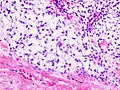

| Histopathologic image of chondrosarcoma of the chest wall. Surgical resection of recurrent mass. H & E stain. | |

Imaging studies - including radiographs ("x-rays"), computerized tomography (CT), and magnetic resonance imaging (MRI) - are often used to make a presumptive diagnosis of chondrosarcoma.[9] However, a definitive diagnosis depends on the identification of malignant cancer cells producing cartilage in a biopsy specimen that has been examined by a pathologist. In a few cases, usually of highly anaplastic tumors, immunohistochemistry (IHC) is required.